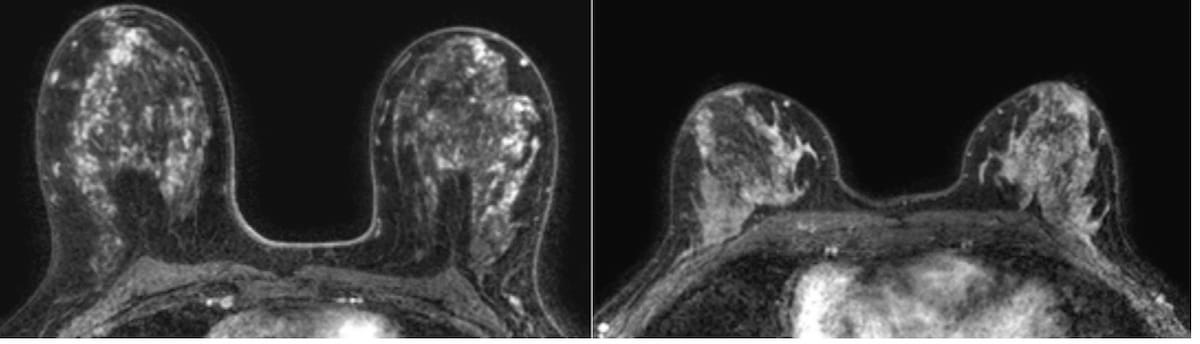

Emerging research suggests that a high volume of enhancing parenchyma on dynamic contrast-enhanced MRI more than doubles the breast cancer risk for women with extremely dense breasts.

Given the increasing prevalence of breast reconstruction, researchers discussed key signs of common complications on magnetic resonance imaging (MRI), ultrasound and other imaging during a recent presentation at the American Roentgen Ray Society (ARRS) 2023 Annual Meeting in Honolulu, Hawaii.